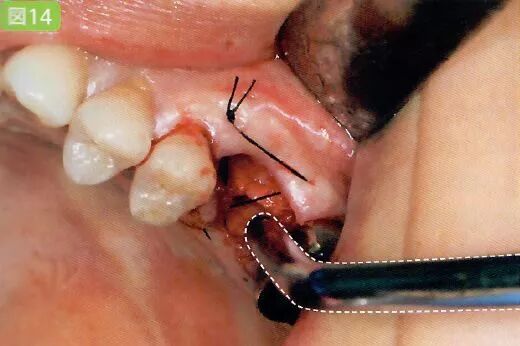

9 缝合

切开的牙龈和牙槽粘膜用针缝合

有出血状况时保证缝合部位的术野

缝合时为了避免针尖刺伤粘膜,需要对舌头和颊粘膜进行排开

用针缝合前吸引牙龈

缝合前用吸唾器吸引切开线区域。缝合后,结扎并截断缝合线前,吸引从切口结扎处溢出的血液。

缝合舌侧牙龈时,为了避免患者的舌头触碰到针尖,根据主治医生的喜好可以使用简易的吸唾器,对舌头进行排开。